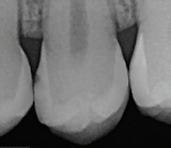

In the endodontic stage, conservative endodontic preparation and obturation with modern techniques are performed as they are for any tooth. All endodontic procedures are performed under an operating microscope to maximize visualization and illumination of the fracture line (Fig 1). The coronal portion of the newly placed gutta percha is removed 2 to 3 mm below the deepest extent of the crack in the affected canal to prepare for intraradicular barrier placement (Fig 2). Gutta percha is also removed 2 to 3 mm into the other noncracked canal orifices in the tooth to prepare for traditional orifice barriers. Microscopic transillumination with a fiber-optic light, in which an LED light probe is placed against buccal or lingual tissues overlying the roots, is utilized to illuminate the root and enhance visualization of the crack (Fig 3). A flowable resin-modified glassionomer or composite resin is then placed in this newly created void from the level of the gutta percha to the floor of the pulp chamber in all canal orifices (Fig 4). A composite resin core is then placed to permanently restore the endodontic access. If a temporary or permanent crown is not placed immediately after the endodontic procedures, the tooth is reduced

Periapical radiograph at the completion of the endodontic protocol. Resin-modified glass ionomer cement is placed as an intraradicular barrier in the distal canal, along the pulpal floor, and as an orifice barrier in the mesial canals.

Fig 1. Microscopic visualization of the radicular extension of the crack (arrows) entering the canal.

Fig 2. Gutta percha removed 2 mm apical to the terminus of the fracture (arrows).